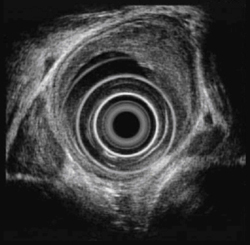

식도암에서 식도초음파 내시경 이미지

[식도암에서 식도초음파 내시경]

위에서 말한 일반적인 식도내시경의 경우에는 식도내강의 표면만을 관찰하도록 되어있어 암이 얼마나 깊이 파고 들어 갔는지는 알기 어려운 단점이 있습니다. 흉부 전산화단층촬영 등의 방법도 있지만 정확한 깊이는 알기 어렵습니다. 초음파 내시경검사는 식도내에 초음파기기를 삽입하여 식도벽을 통해 검사를 시행하므로 식도암의 침범 정도에 대해 세밀하게 알 수 있습니다. 뿐만 아니라 식도암이 대동맥이나 척추, 기관 같은 식도 주변의 기관으로의 침범여부도 정확히 알 수 있으며, 암의 식도 주변의 림프절 침범여부도 비교적 정확히 알 수 있으며, 식도를 통하여 조직검사를 할 수 도 있습니다.